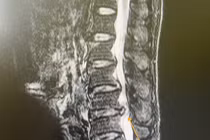

(khoahocdoisong.vn) - Bệnh nhân bị hẹp ống sống có thể được làm các xét nghiệm chẩn đoán hình ảnh để chẩn đoán bệnh gồm: cộng hưởng từ cột sống hoặc chụp cắt lớp cột sống có tiêm thuốc cản quang vào khoang dưới nhện, đôi khi cả 2 phương pháp.

(khoahocdoisong.vn) - Hẹp ống sống thắt lưng tiến triển khi mà ống sống và lỗ liên hợp (nơi các rễ thần kinh thoát ra khỏi ống sống) ở thắt lưng trở nên hẹp và tạo nên áp lực lên tủy sống và/hoặc các rễ thần kinh.